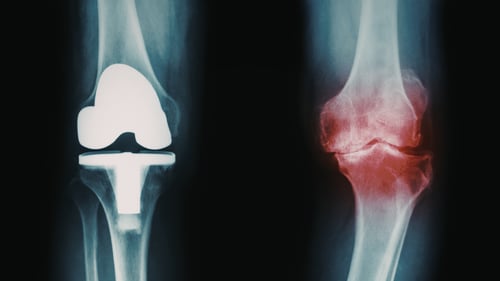

Bone Density

DEXA scans assess bone density, which is crucial for reducing fracture risk and supporting overall structural health. Higher bone density contributes to sustained physical performance and long-term well-being.